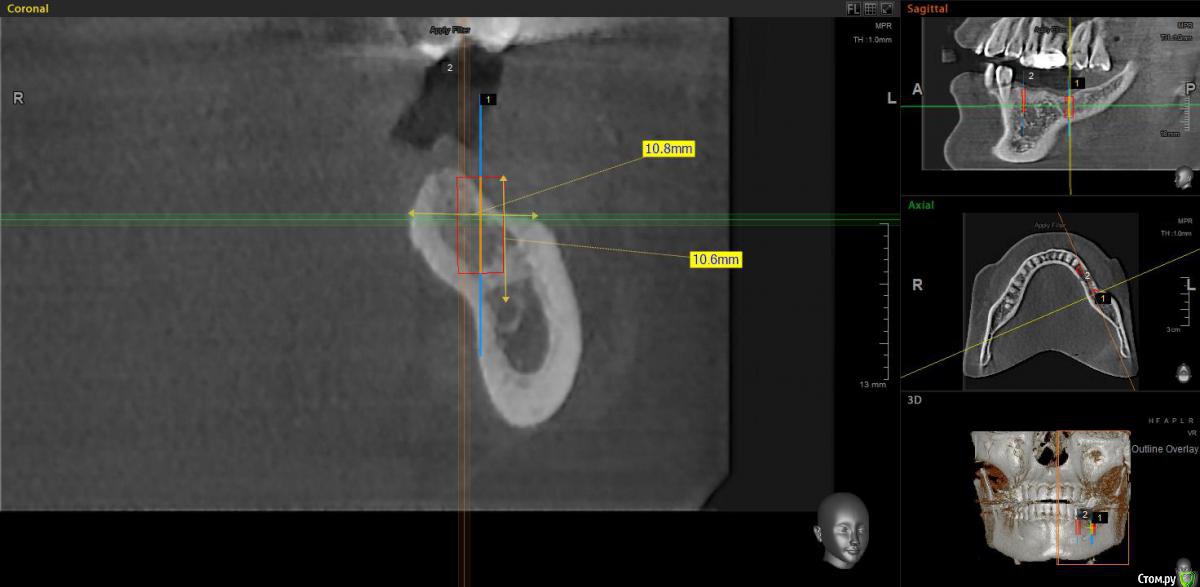

moises Опубликовано 30 ноября, 2019 Поделиться Опубликовано 30 ноября, 2019 Добрый вечер,коллеги.У пациентки отсутствуют зубы 35,36,37.Планирую установить имлантаты Neobiotek в область 35 и 37.В области 35 без п проблем проходит 4.0X10, а в области 37 имеется вестибулярный дефект.Планирую установить имплантат 4,0X8 и вестибулярно добавить ксено+ауто со скребка 50 на 50.Вопрос такой-что предпочтительнее при таком дефекте-использовать небольшую мембрану(Collprotect от Botiss,наример) с пинами или винтами,или спейсер?И еще вопрос- если я делаю разрез от 35 и продолжаю его до 37(или даже дистальнее,чтобы набрать аутокость скребком),нужно ли мне мобилизовать лоскут на всем протяжении?Или только в дистальной части,где будет НКР? Ссылка на комментарий

moises Опубликовано 5 декабря, 2019 Автор Поделиться Опубликовано 5 декабря, 2019 так какая там ситуация в области 36? что там с костью и слизистой? и вы уверенны с позицией 37? он смотрит в щечный бугор 27! сделайте фото, покажите больше срезов, с ортопедом продумайте все варианты протезированияи уверен, вам подскажут хороший вариант протезирования. вы вопрос поставили конкретный "мембрану или смартбилдер" и Александр верно вам ответил хотя осмелюсь предположить, сам бы он выбрал другой вариант ))) на ankylosСместить язычнее-выраженное поднутрение .Или ось сместить,чтобы выйти на небный бугор 26?Протезировать буду сам. Ситуация в области 36 Ссылка на комментарий